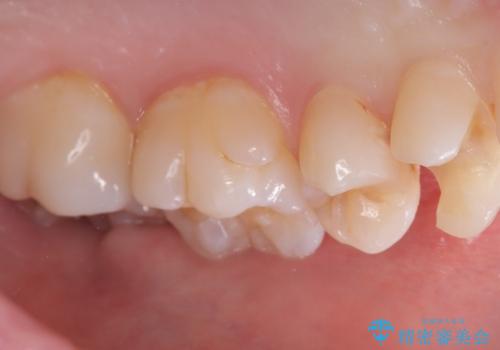

- 主訴:左上真ん中らへんの歯が欠けてしみるので治したい

審美性、適合性の良いセラミックインレーでのやり替えとなりました。

左上4近心に実質欠損を認め、遠心から咬合面にかけてはCR修復が施されていたため、MODインレー窩洞としました。

インレー接着操作時はラバーダム防湿を行っています。